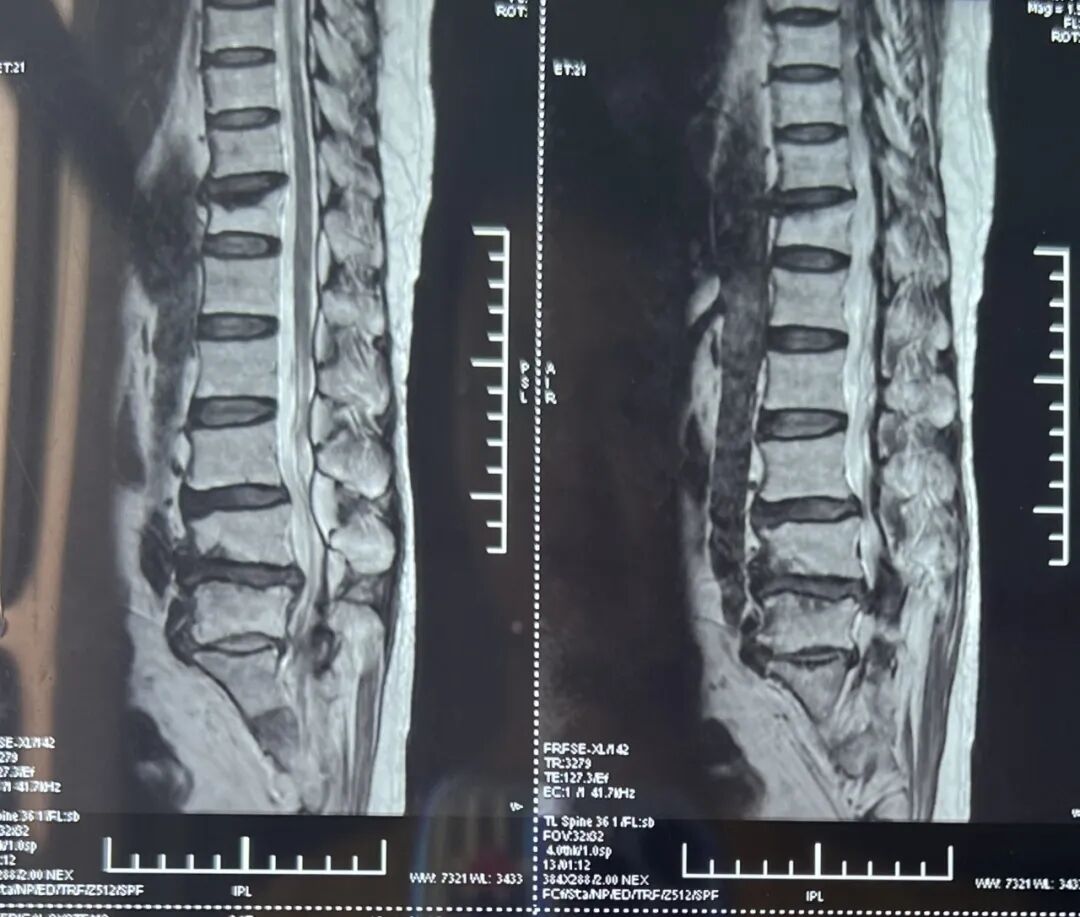

图片

(术前MR,L4-5椎间盘突出)